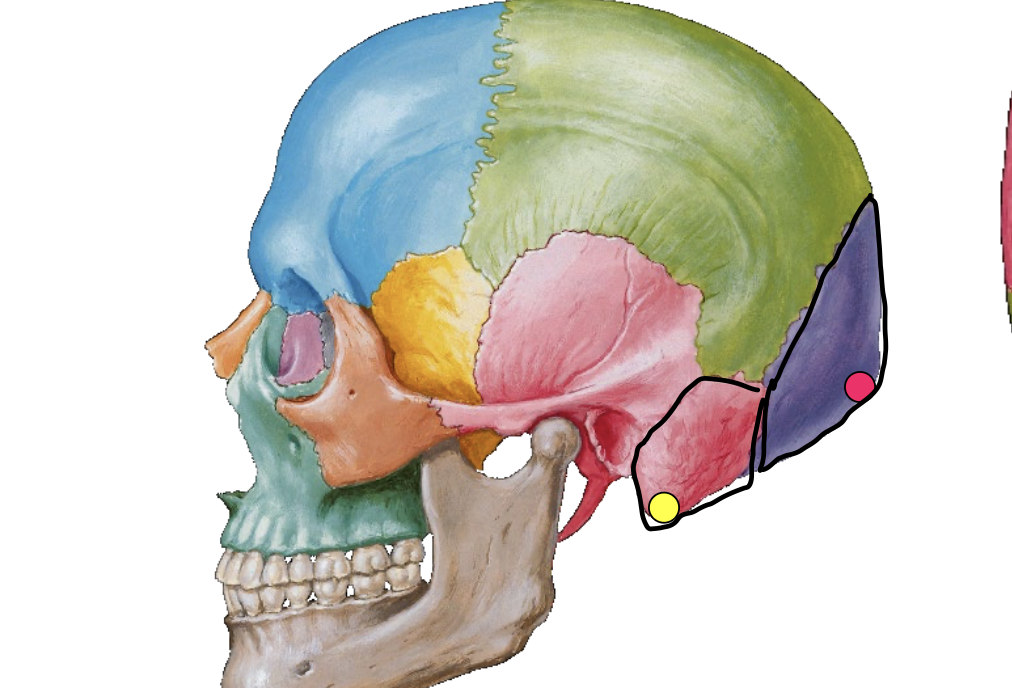

What is the pink dot locating in this image?

External occipital protuberance

What is the yellow dot locating in this image?

Mastoid process